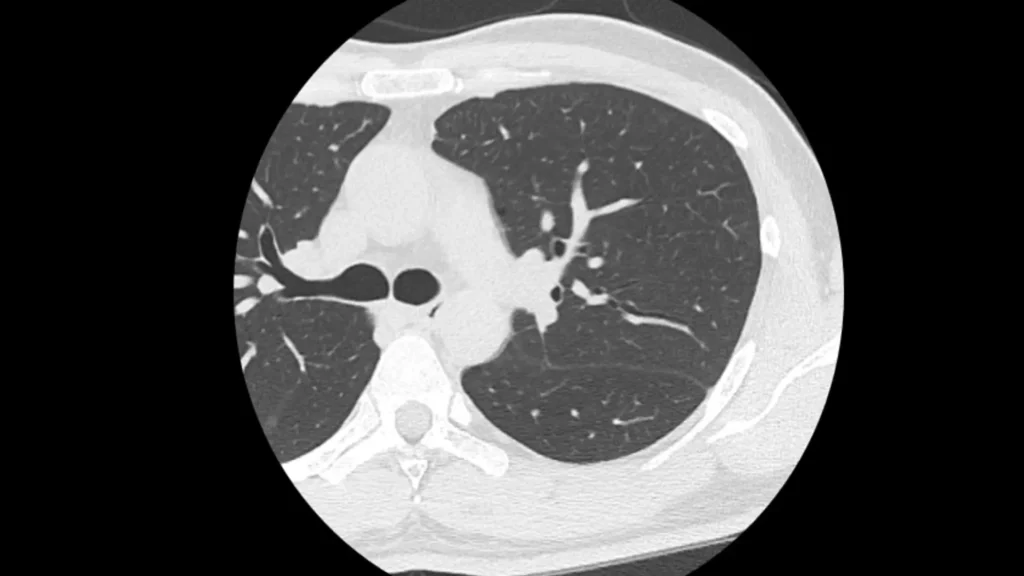

以下は実際に肺がんが見つかった患者さんのCTとレントゲンの比較です。

CTでは黄色矢印の影(すりガラス影)がわかりますが、レントゲンでは確認が難しいです。

実際のCT画像所見

以下に

①:正常の肺

②:炎症の影

③:肺がん

④:③の患者さんのX線画像

を掲載します。

やはり、④のX線では肺がんを指摘するのは難しいですが、③でははっきり影がわかります。

ちなみにこの患者さんは、健診のX線では異常を指摘されませんでしたが、咳があったため心配で受診し、CTを撮ったところ肺がんが見つかりました。